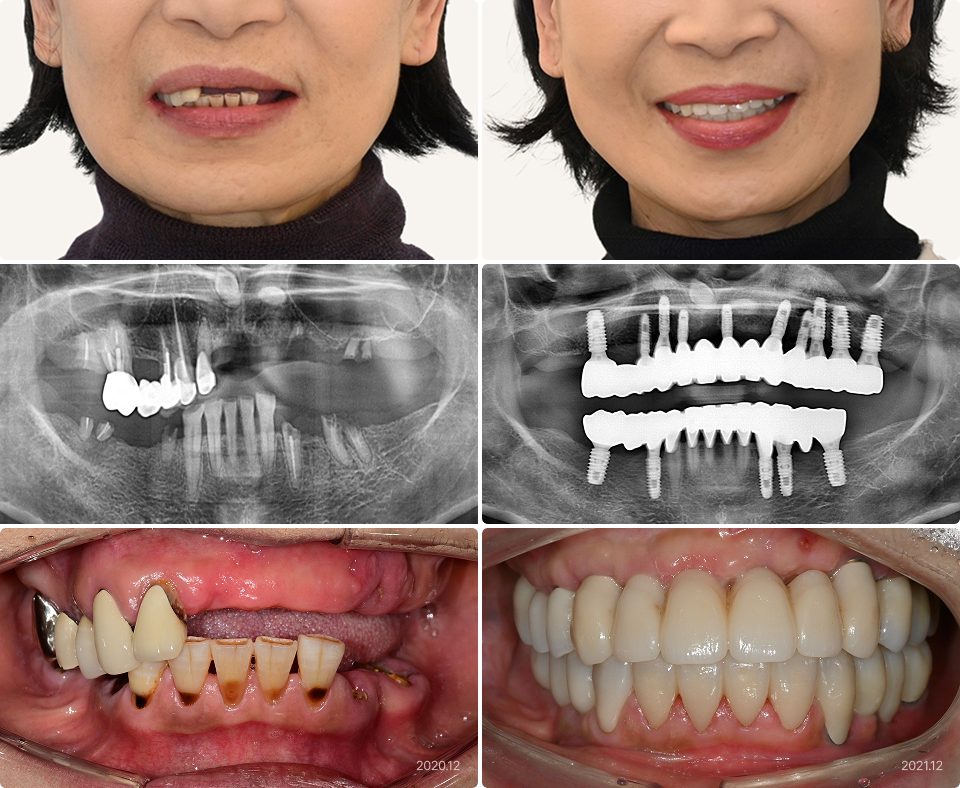

64세, 여

“잇몸뼈가 없어서 대학병원에 가야한다고 들었는데,

하늘에치과에서 가능할까요?”

치료기간 : 12개월

치료 전

치료 후

• 이른 나이부터 틀니 사용으로 잇몸뼈 퇴축이 심함

• 임플란트는 대학병원에서 가능하다고만 듣고 낙심하였음

• 수면 상태에서 한 번의 수술로

15개의 임플란트 식립 및 광범위한 뼈이식

• 환자분 개인 사정으로 기간은 지연되었지만

광범위한 뼈이식도 순조롭게 완성